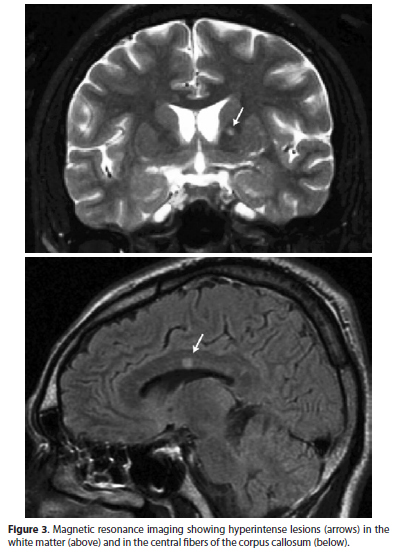

Susac syndrome (SS) is an arterial occlusive disease associated with a triad of symptoms: encephalopathy, hearing loss and multiple branch retinal artery occlusions (MBRAO)(1-3). Other findings include diffuse neurological signs as headache, psychiatric disturbances, cognitive changes, memory loss, and confusion that may rapidly progress to dementia. Magnetic resonance imaging (MRI) shows a distinctive pattern of hyperintense white matter lesions (on T2 and FLAIR sequences) with preferential involvement of the central callosal fibers and the development of central callosal holes as the active lesions resolve(4). SS is presumably autoimmune in origin and treatment is still uncertain, but steroids, cyclophosphamide, azathioprine, plasmapheresis and intravenous immunoglobulin have been used with some success to halt disease progression(4,5).

Three weeks later the patient developed tinnitus and sudden right hearing and visual loss followed by headache, apathy, confusion and somnolence. A repeat neurological examination showed the patient to be torporous, with brisk reflexes, bilateral extensor plantar responses and pseudobulbar speech. Visual acuity was 20/100 in OD and finger counting in OS. The fundus examination revealed MBRAO involving the superonasal and the infero-temporal branches of the central retinal artery in OD (Figure 2) and a CRAO in OS. The MRI scan disclosed several small areas of hyperintense signal on T2-weighted images in the gray and white matter, including the involvement of the central fibers of the corpus callosum (Figure 3). A lumbar puncture revealed clear and colorless cerebro-spinal fluid with 9 cells (92% lymphocytes) and a protein level of 126 mg/dl. Retinal fluorescein angiography confirmed MBRAO in OD and a CRAO in OS.